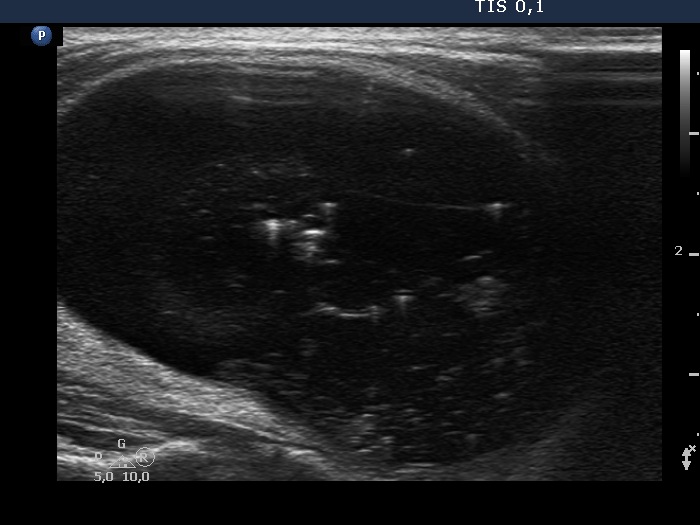

One year before the present examination (first row of images)

Clinical presentation: A 55-year-old man was referred for examination of a lump in the neck which has developed for 2 weeks.

Palpation: an elastic nodule in the right lobe.

Functional state: euthyroidism (TSH 0.97 mIU/L).

Ultrasonography. The thyroid was echonormal. A large nodule occupied almost the entire right lobe. This was an almost completely cyst with a tiny echonormal solid part at the ventral wall. The nodule had numerous large comet-tail artifacts and showed no vascularity. The dimensions of the nodule were 24x27x48 mm - 16.3 mL.

Only 2.5 mL brown fluid could be aspirated from the cyst. Cytology resulted in benign cystic degeneration.

Suggestion: repeat examination in 4 months.